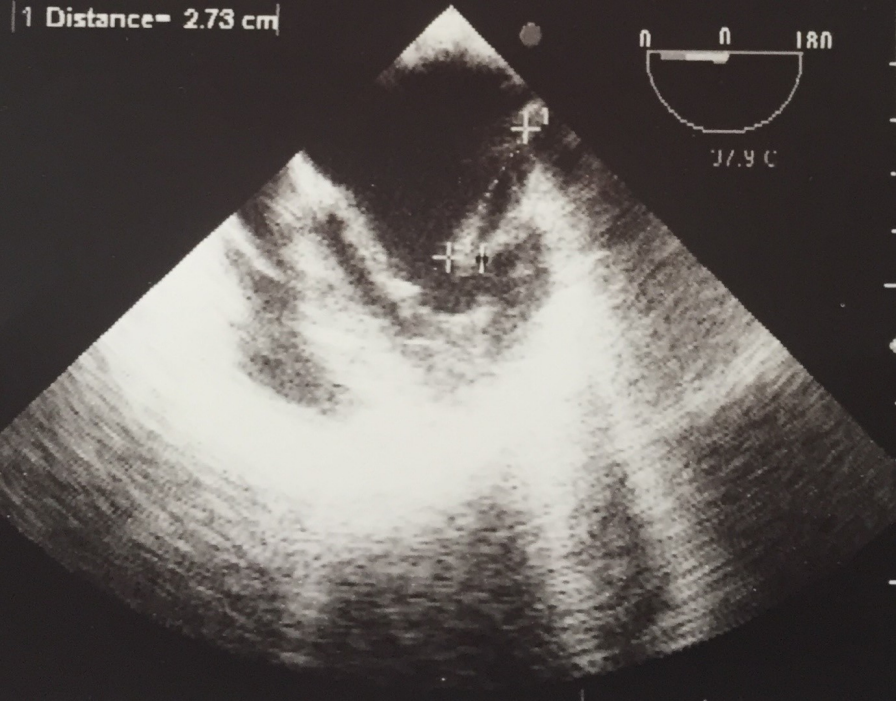

The nosocomial mortality rate was zero (Table 1 [Tab. 1]). However, 14 patients (70%) underwent surgical treatment. Four patients (20%) underwent valve defect repair and 10 patients (71%) underwent the valve replacement. Blood cultures were positive in only 1 patient, which yielded Streptococcus viridans group. The most common underlying disease (95%) was cardiovascular disease. Only one 2-year-old boy (5%) had an additional ventricular septal defect (VSD). Positive CRP was seen in 3 (15%) patients. 5 patients (25%) had an erythrocyte sedimentation rate greater than 20 mm in the first hour. Only one patient (5%) showed leukocytosis. Moreover, TEE was positive for all (100%) patients, and vegetation was seen in all. The vegetation size was large in 1 patient, i.e., almost 3 cm (Figure 1 [Fig. 1]). The most frequently involved valve was the mitral (bicuspid) valve (40%) followed by aortic valve (35%) and tricuspid valve (25%; Table 2 [Tab. 2]). All patients had a positive history of previous antibiotic administration and hospitalization in other hospitals before presenting to our center. The most frequently administered antibiotic was vancomycin in 70% of cases. Eighteen patients (90%) were discharged after hospitalization in good health condition. while 2 patients (10%) suffered from temperature at 38ºC at discharge.

TEE, when clinically indicated, was performed as described previously [18]. The investigators assessed the presence of following features: new dehiscence, vegetation, abscess, and new moderate or severe valvular regurgitation. An irregularly shaped echogenic mass, which was attached to a valve or myocardial surface, was considered as vegetation. The vegetation lengths were measured in different planes, and the maximal length was chosen. Also, a thickened area or mass with a heterogeneous echogenic or echoluscent appearance was considered as an abscess. Semi-quantitative analysis was performed to determine the acuity of the valvular regurgitation using color flow Doppler echocardiography.